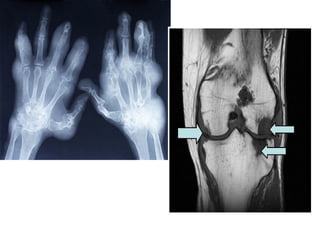

Gout

overload of uric acid in the body. This

Gout • Gout isa disease that results from an overload of uric acid in the body. This overload of uric acid leads to the formation of tiny crystals of urate that deposit in tissues of the body, especially the joints. When crystals form in the joints it causes recurring attacks of joint inflammation (arthritis). Chronic gout can also lead to deposits of hard lumps of uric acid in and around the joints and may cause joint destruction, decreased kidney function, and kidney stones.